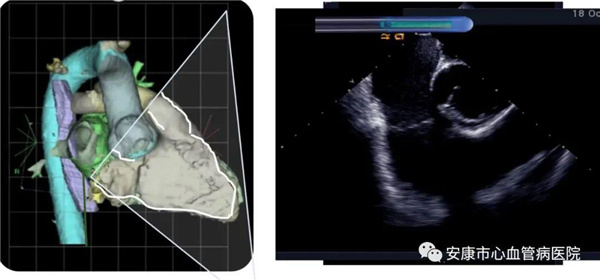

心律失常團隊在11月6日為患者在ICE引導(dǎo)下行房撲射頻消融術(shù)。穿刺左鎖骨下靜脈,導(dǎo)絲走行證實了合并永存左上腔靜脈。穿刺右股靜脈,分別送入心腔內(nèi)超聲導(dǎo)管和消融電極,超聲下建立右心室、右心房、左心室、左心房、二尖瓣和三尖瓣及三尖瓣峽部模型。ICE就像術(shù)者多了一雙天眼,可以對心臟內(nèi)部結(jié)構(gòu)一目了然,360度無死角觀察心臟結(jié)構(gòu),可以做到“所視即所及”。建模后,消融三尖部峽部,房撲很快終止,轉(zhuǎn)為竇性心律,手術(shù)獲得成功!手術(shù)用時僅70分鐘,術(shù)后病情穩(wěn)定,安全返回病房。wWU安康新聞網(wǎng)

心腔內(nèi)超聲(Intracardiac Echocaiography ICE)是將微型的換能器安裝在心導(dǎo)管的尖端,再經(jīng)外周血管(動脈或靜脈)送至心腔,換能器發(fā)射聲波,然后將接受到的回波經(jīng)計算機處理后形成超聲圖像。由于換能器放置在心腔內(nèi),不受空氣等因素的干擾,因此比經(jīng)食道超聲檢查圖像更加清晰,可以辨別心內(nèi)的細微結(jié)構(gòu),臨床上主要用于指導(dǎo)心律失常的射頻消融治療。wWU安康新聞網(wǎng)